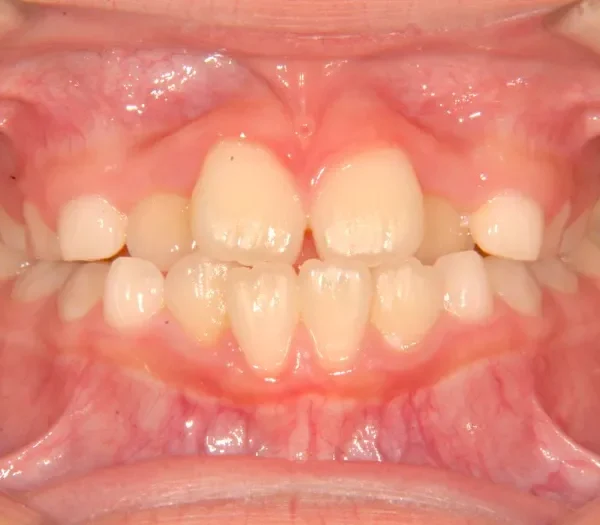

• 治療終了後

治療終了後

治療回数44回、5年5ヶ月の治療期間で矯正治療を終了しました。

主訴が改善され、ご満足頂きました。